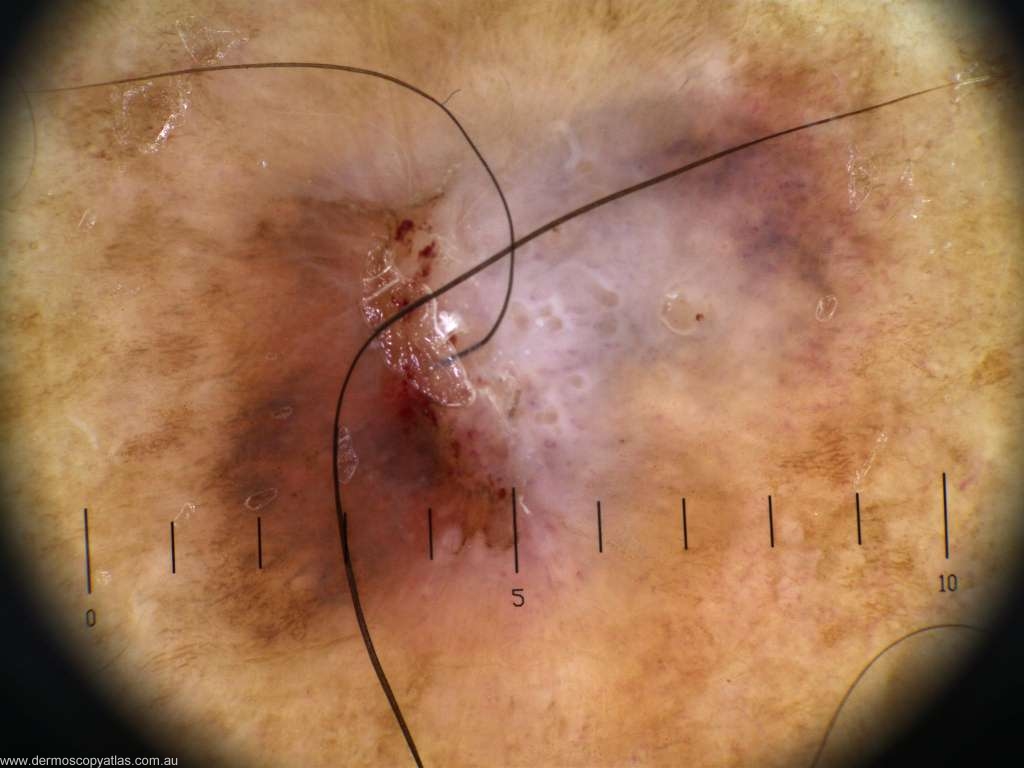

Case 3. 52 year old male auto electrician. 6 weeks of bleeding. Unsure of the appearance prior to bleeding.

Question: What is your diagnosis? Consider Junctional nevus with regression, Melanoma, Atypical Spitz, Lichen planus like keratosis or Pigmented IEC

Answer: Histology: Intense lichenoid regression occurring within a flat seborrhoeic keratosis/solar lentigo.